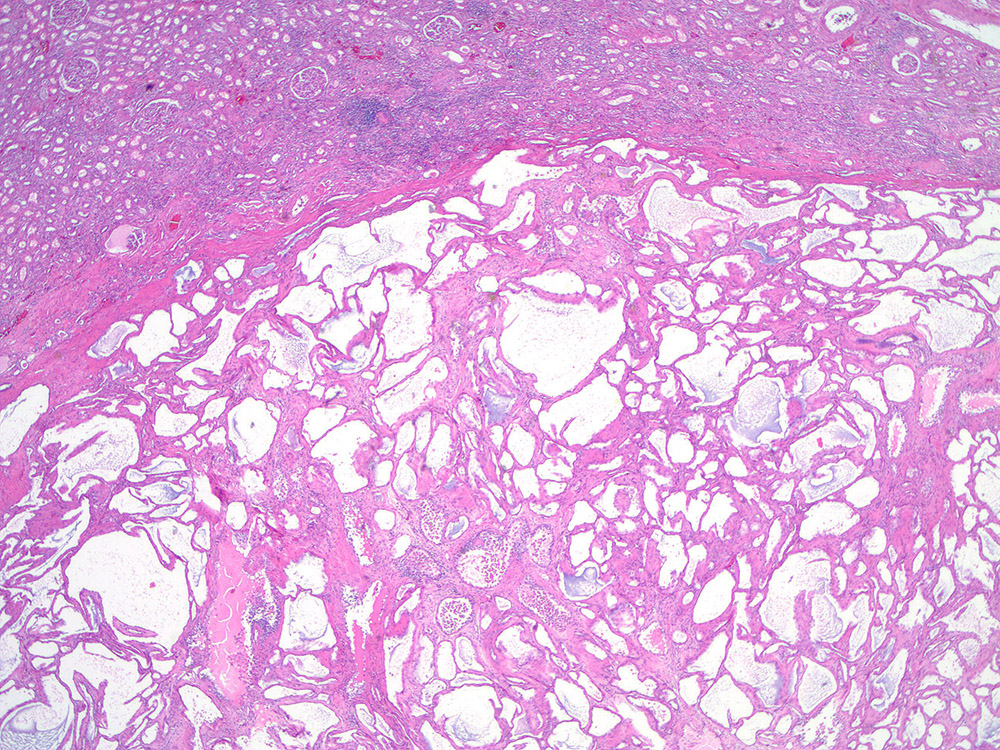

Consensus grade: Tubulocystic RCC

Renal mass- 62 year old woman